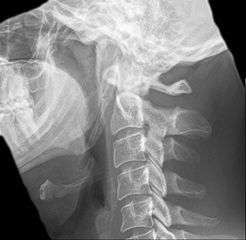

Anteroposterior and lateral radiographs of cervical spine showing ossification of the stylohyoid ligament on both sides

Imaging is important and is diagnostic. Visualizing the styloid process on a CT scan with 3D reconstruction is the suggested imaging technique.[6] The enlarged styloid may be visible on an orthopantogram or a lateral soft tissue X ray of the neck.